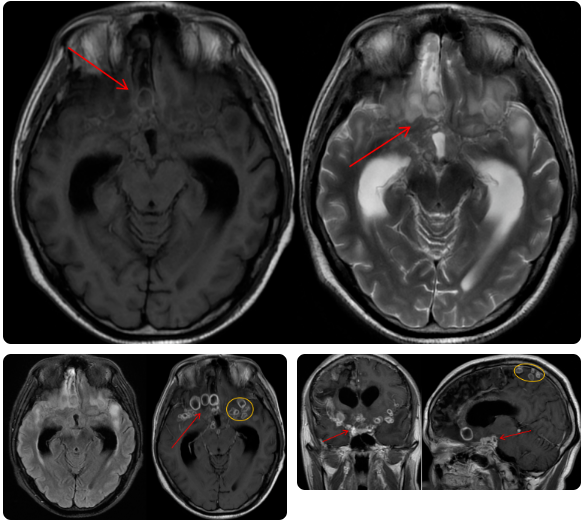

相比CT,MRI对脑膜、脑实质的显示更清晰,增强扫描还能让炎症病灶“亮”起来,是诊断颅内感染的重要工具。

MR表现:颅内脑沟裂池内见多发明显环形强化灶,部分融合呈蜂窝状簇状(黄色),以鞍上池、双侧外侧裂池为著,局部波及胼胝体。

影像诊断:结核性脑膜炎

头颅 MRI 是其中重要的辅助检查,其表现为大脑基底池脑膜增厚为主,合并簇状分布的脑膜结节,增强扫描结节成环形强化等征象,以及继发脑积水、脑内前循环血管炎、脑梗死等。

本例患者有明确的肺结核病史,MRI表现为典型的脑膜环形强化、簇状分布,结合脑脊液检查(通常可检出结核杆菌或特异性抗体),诊断结核性脑膜炎是确凿的。